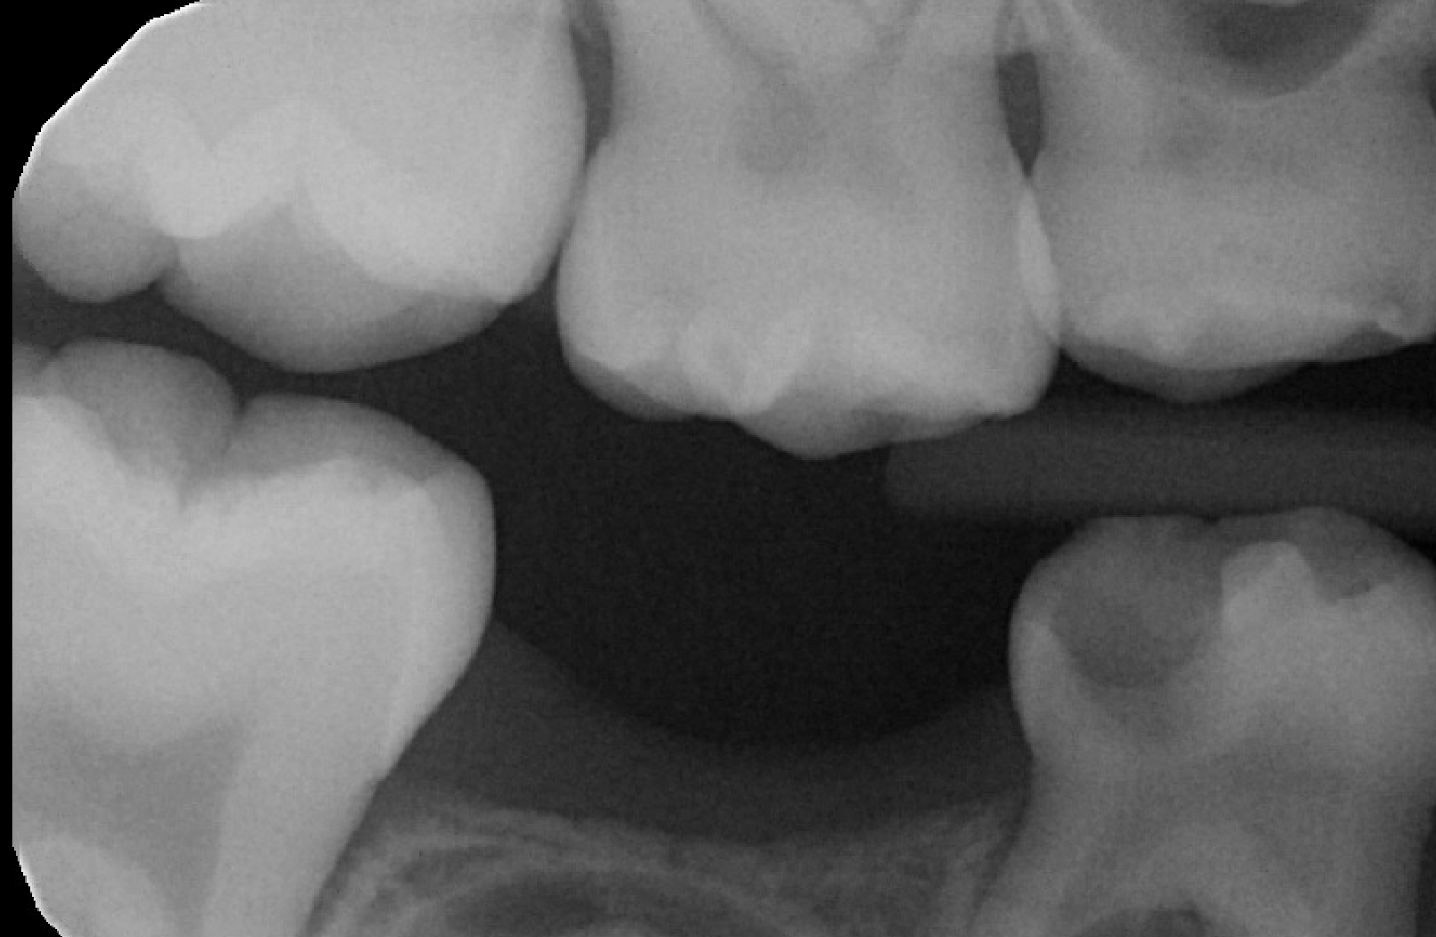

Patient presented to NYUCD to visit the dentist for the first time in 2017. These BWs and PAN were taken then.

Figures 9 & 10: Preoperative bitewings of Right and Left

Figure 11: Preoperative Panoramic image

Unfortunately, due to the amount of dental treatment needed and number of dental visit needed, patient and mother never returned back to NYU dental clinic.

Due to the clinical carious lesions present - 2 BW radiographs were recommended to observe any interproximal carious lesions (also to update the treatment plan that was never fulfilled) and PA#8 to observe the location of mesiodens and any update in eruption of #8 or the mesiodens.

Radiographic Interpretation revealed: Carious lesions in #3-O, #A-O, #14-O, #19-OB, #K-MOD, root tip present in tooth #L, #30-O, Mesiodens present ( disrupting the proper eruption of tooth #8) ***